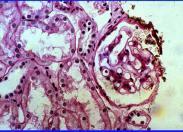

膜增生性腎小球腎炎癥狀

• 膜增生性腎小球腎炎

628健康網為您分享有關膜增生性腎小球腎炎的癥狀,膜增生性腎小球腎炎的治療方法,膜增生性腎小球腎炎的預防知識,膜增生性...